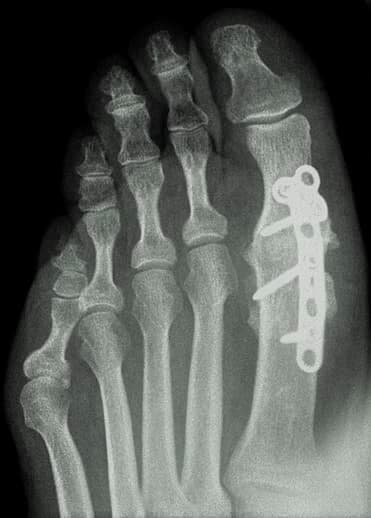

Juanetes

Esta afección tan común, mayoritariamente en las mujeres, es molesta a la hora de calzarse y de caminar, ya que causa dolor sobre la articulación, la cual empeora con la presión del calzado. Con los tratamientos quirúrgicos que ofrecemos, mediante la cirugía de mínima incisión, podemos resolver la patología del juanete, permitiendo al paciente caminar desde el primer momento, marchándose a casa sin dolor y con una recuperación mucho más rápida que mediante las técnicas tradicionales.